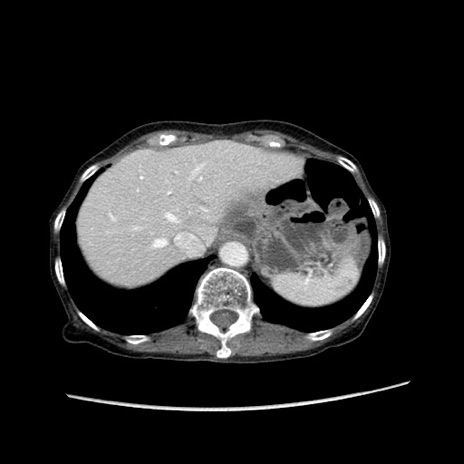

症例25(横断像)

【症例】80歳代女性

【主訴】胸のつかえ感

【現病歴】約9時間前に食後から胸のつかえた感じあり、嘔吐あり、来院。

【既往歴】胃癌(全摘)、胆摘、虫垂炎

【身体所見】心窩部に圧痛あり、反跳痛なし。

【データ】WBC 5700、CRP 0.05